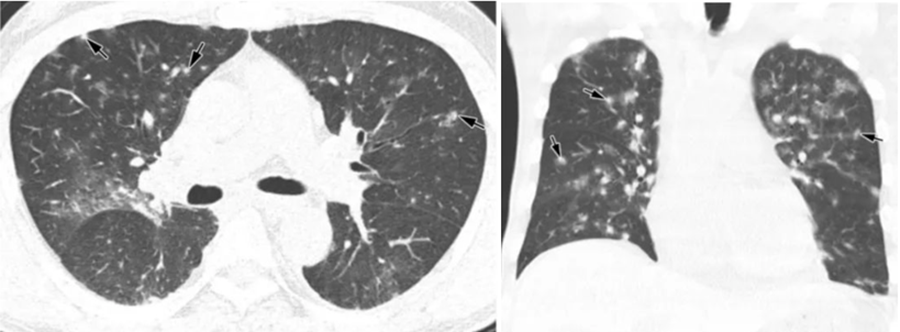

(6)免疫抑制患者的经验性抗CMV指征:①宿主特征:肺移植术后,造血干细胞移植术后。②临床特征:双肺弥漫性磨玻璃影伴小叶间隔增厚。③治疗推荐:更昔洛韦:5 mg/kg q12h。